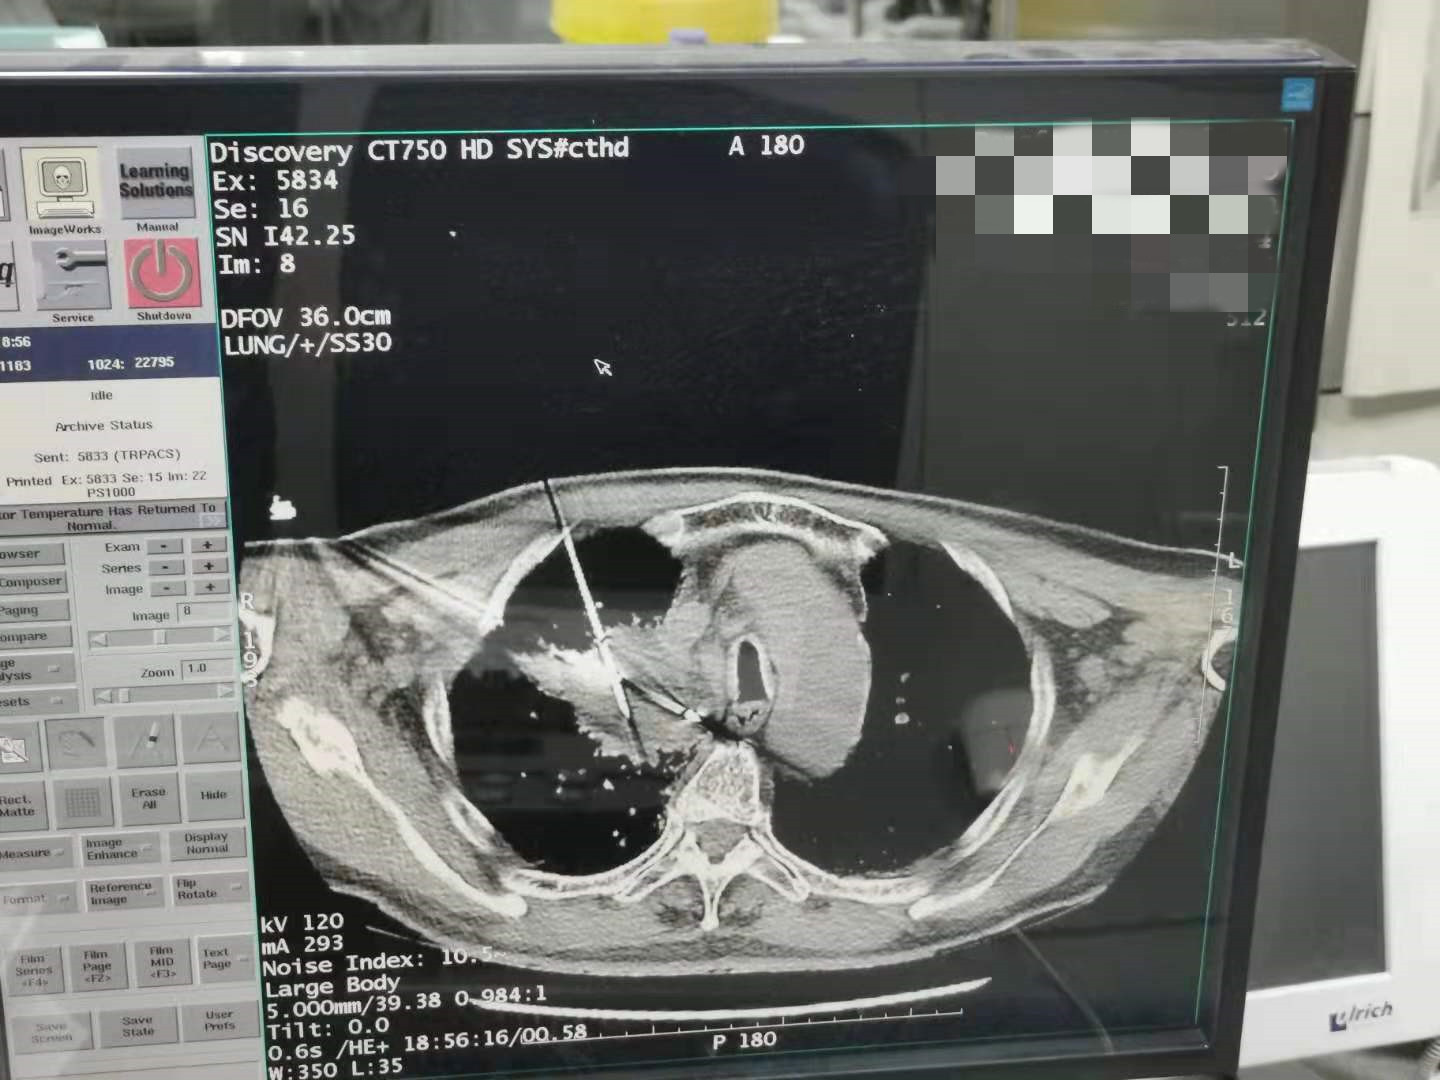

上一篇:2021年7月份臀部氩氦刀手术